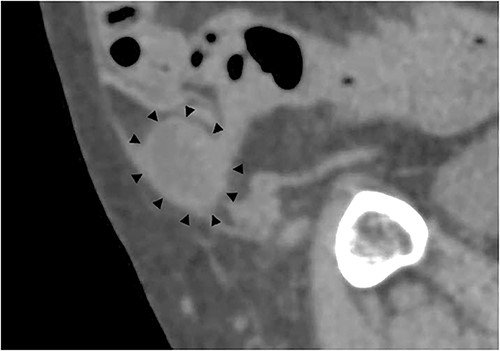

A 79-year-old male patient with a medical history of right inguinal hernia presented to the emergency department with right inguinal swelling and pain. We found the inguinal swelling, which extended toward the head, to be atypical. In addition, contrast-enhanced computed tomography (CT) scan revealed that a portion of the small intestine was incarcerated between the internal and external oblique muscles, and the hernia contents had prolapsed cranially from the hernial orifice. Furthermore, the sagittal view revealed that the contents of the hernia had prolapsed ventrally and not along the spermatic cord (Figs 1 and 2). Therefore, we diagnosed it as a right interparietal inguinal hernia, and laparoscopic hernia repair was planned. Owing to the fact that the manipulative reduction was difficult, we planned to release the incarceration first.

Contrast-enhanced CT scan; an incarcerated bowel was observed in the right inguinal region; the small bowel was incarcerated between internal and external oblique muscles; the white arrow indicates the internal oblique muscle, and the white triangles indicate the external oblique muscle.

Sagittal section of contrast-enhanced CT; the black triangles indicate the incarcerated small bowel.